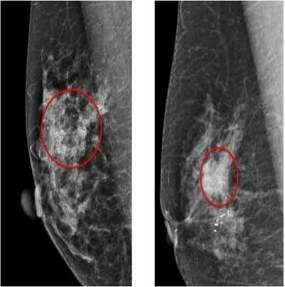

全數字化乳腺X線機